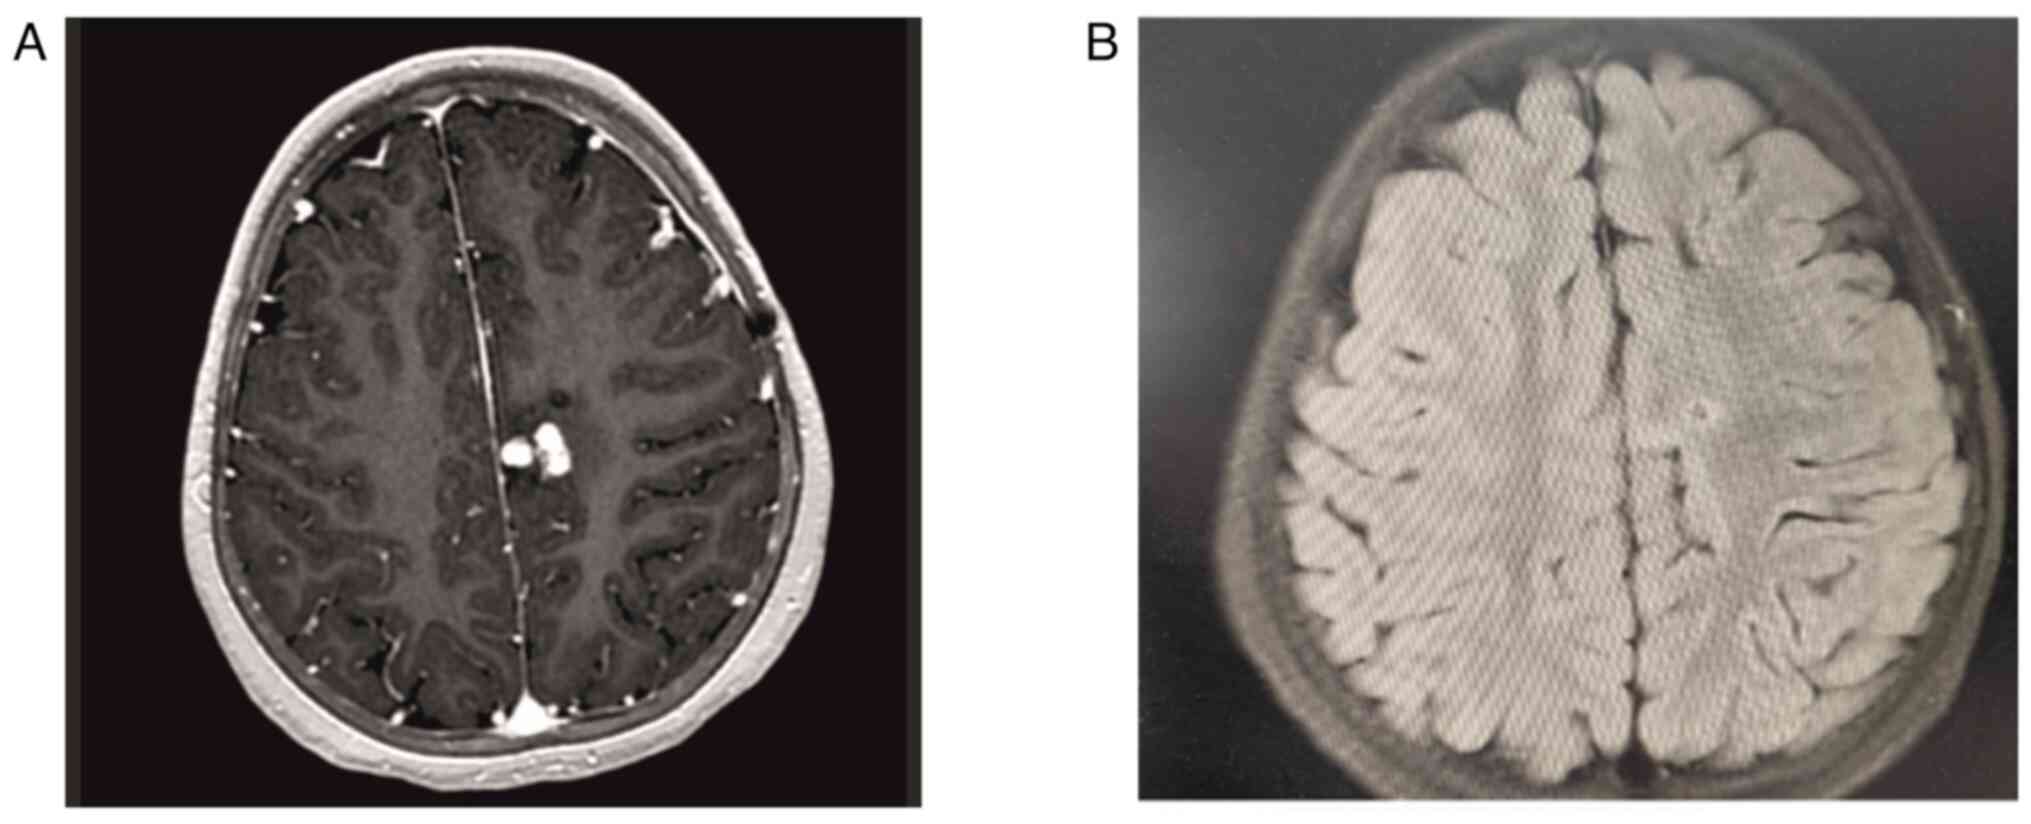

Intracranial tuberculoma represents one of the most severe complications of central nervous system tuberculosis (TB), with an incidence that is relatively low. In cases of intracranial tuberculoma, patients may develop drug toxicity and/or immune reconstitution inflammatory syndrome (IRIS) while receiving anti‑TB treatment. The current study presented the case of a seven‑year‑old female patient with intracranial tuberculoma who developed drug‑induced hepatotoxicity and IRIS during the course of treatment. During the follow‑up of the patient, anti‑TB drug‑induced hepatitis developed, which led to the discontinuation of the drug twice. In the seventh month of treatment, cranial MRI showed the progression of tuberculoma lesions. The possibility of IRIS or treatment failure was considered and the treatment was restarted with steroids and non‑hepatotoxic anti‑TB drugs. With steroid and anti‑TB treatment, the lesions regressed almost completely and the neurological deficit regressed. Patients receiving treatment should be followed up closely due to the possible side effects of anti‑TB drugs, especially IRIS, which develops as an immune restructuring response during the recovery of the immune system.

Figure 1

Figure 2

Figure 3

Figure 4

Figure 5